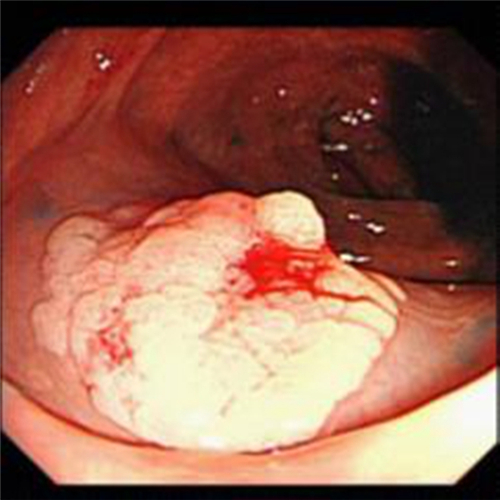

直腸息肉切除

直腸息肉手術過程

直腸息肉糜爛的